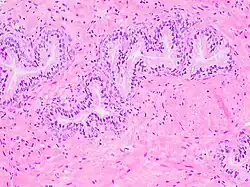

Histology of prostate with gradually increasing simple atrophy from left to right, H&E stain. Crowding and angulation may mimic that of adenocarcinoma, but there is nuclear basophilia rather than atypia, and occasional basal cells can still be seen.

The prostate consists of glandular and connective tissue.[2] Tall column-shaped cells form the lining (the epithelium) of the glands.[2] These form one layer or may be pseudostratified.[4] The epithelium is highly variable and areas of low cuboidal or flat cells can also be present, with transitional epithelium in the outer regions of the longer ducts.[10] Basal cells surround the luminal epithelial cells in benign glands. The glands are formed as many follicles, which drain into canals and subsequently 12–20 main ducts, These in turn drain into the urethra as it passes through the prostate.[4] There are also a small amount of flat cells, which sit next to the basement membranes of glands, and act as stem cells.[2]

The connective tissue of the prostate is made up of fibrous tissue and smooth muscle.[2] The fibrous tissue separates the gland into lobules.[2] It also sits between the glands and is composed of randomly orientated smooth-muscle bundles that are continuous with the bladder.[11]